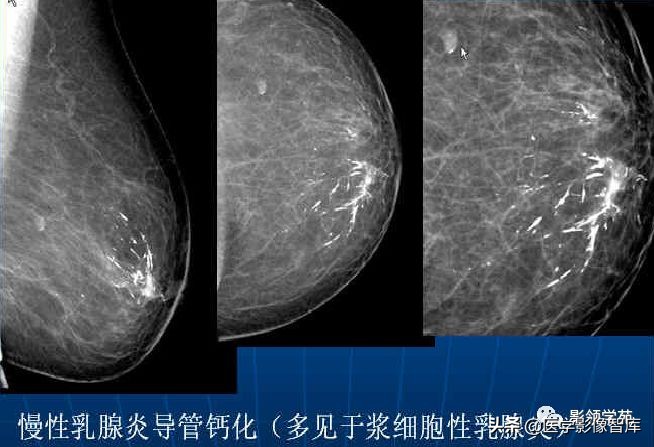

5.Large Rod-like, Plasma cell mastitis

杆状钙化,沿着导管分布,有时呈分支状,通常见于60岁以上妇女。当小于1 mm和导管内原位癌的线样钙化鉴别困难。

浆细胞性乳腺炎,又叫导管扩张症,是导管内的脂肪性物质堆积、外溢,引起导管周围的化学性刺激和免疫性反应,导致大量浆细胞浸润。反复发作,破溃后形成瘘管,可以继发细菌感染,长久不愈。所以说是一种特殊的乳腺炎症。

右乳慢性炎症,导管钙化